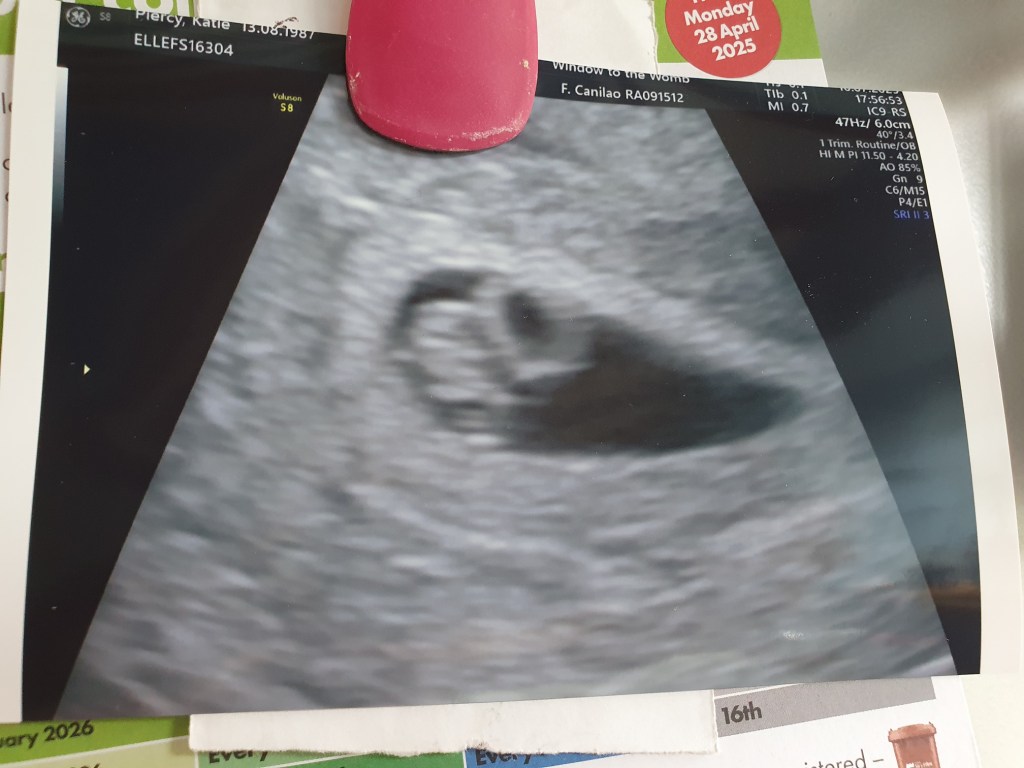

Due to the fact it was an early scan it needed to be internal. I was pretty disappointed as I was tired of people sticking magic wands inside me, and was looking forward to the belly scans. But despite this inconvenience it was exciting as up on the screen came a couple of blobs, and there a flickering heartbeat.

The blobs were the embryo, its egg sac, which was as big as it, and the uterus. There wasn’t any real baby form, just blobs, but the heartbeat was exciting.

The nurse informed me I had some kind of bruising, which was normal as the womb stretched, but which might cause spotting, and the fibroid I was already aware of, but that everything was healthy and looking good.